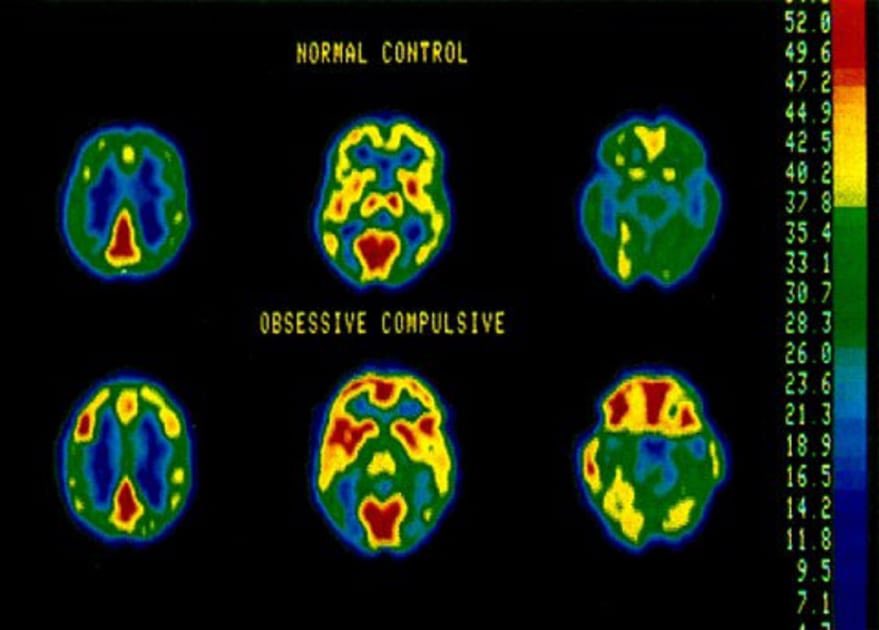

We had the chance to chat with fearne cotton for #OCDAwarenessWeek. We talked about the realities of living with OCD — a condition that’s often misunderstood. OCD goes far beyond just being “neat” or “clean”. It’s a complex mental health problem that can affect us in ways most